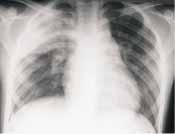

Las neumonías bacterianas ocurren en asociación con inhalación de estos agentes infecciosos dentro el espacio aéreo, lo cual conlleva al desarrollo de edema inflamatorio y exudado en los acinos, causando consolidación de los espacios aéreos. En las radiografías de tórax las consolidaciones se manifiestan como imágenes densas, de distribución lobar o segmentaria. El broncograma aéreo aun cuando no siempre visible, es característico. (Figura 7).

FIGURA 7. Proyección AP de tórax con consolidación neumónica del lóbulo

superior derecho con imagen típica de broncograma en su interior.